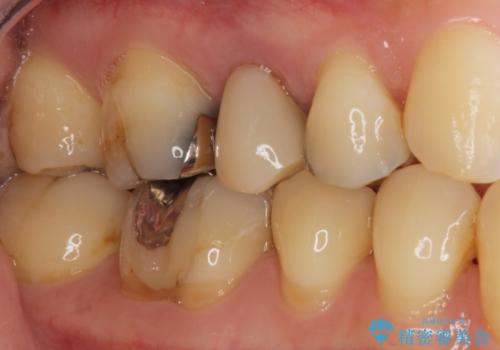

- 歯が欠けてしまったことを主訴に来院された患者様です。

欠けている奥歯(左上5)は失活歯で、保険内の銀の詰め物(メタルアンレー)で治療されていました。

金属の詰め物と土台を除去し、ファイバーコア(金属を使わない強くてしなやかな土台)を植立したのちセラミッククラウンによる補綴治療を行いました。

精査したところ、右上の奥歯(右上5)に根尖病変を認めたため、こちらは根管治療後にセラミッククラウンによる補綴を行いました。